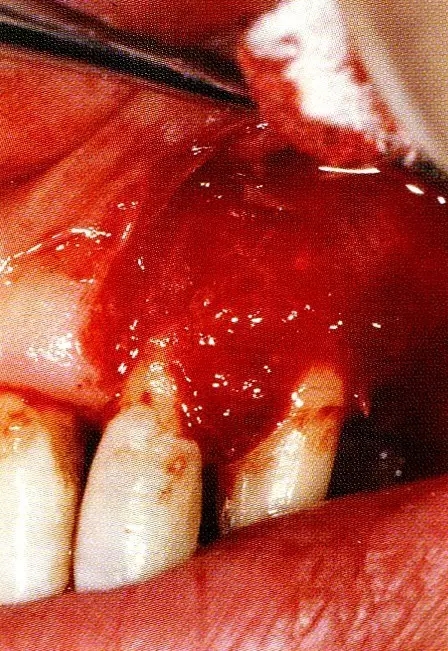

案例3   針對3壁性垂直性骨缺損使用非吸收性膜進行再生治療,再翻瓣時進行骨形態(tài)修整的病例。

▲圖7-1  左下6近中可觀察到3壁性垂直性骨缺損。此病例考慮到齦瓣供血關(guān)系,在前磨牙部位進行了減張切開,沒有進行縱切開。并利用刮治器、牙周外科用車針進行了徹底的骨缺損部位搔刮。